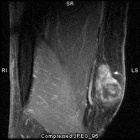

68 year old female with painless mass in right forearm

Zoom image: Radiological image Radiological image.